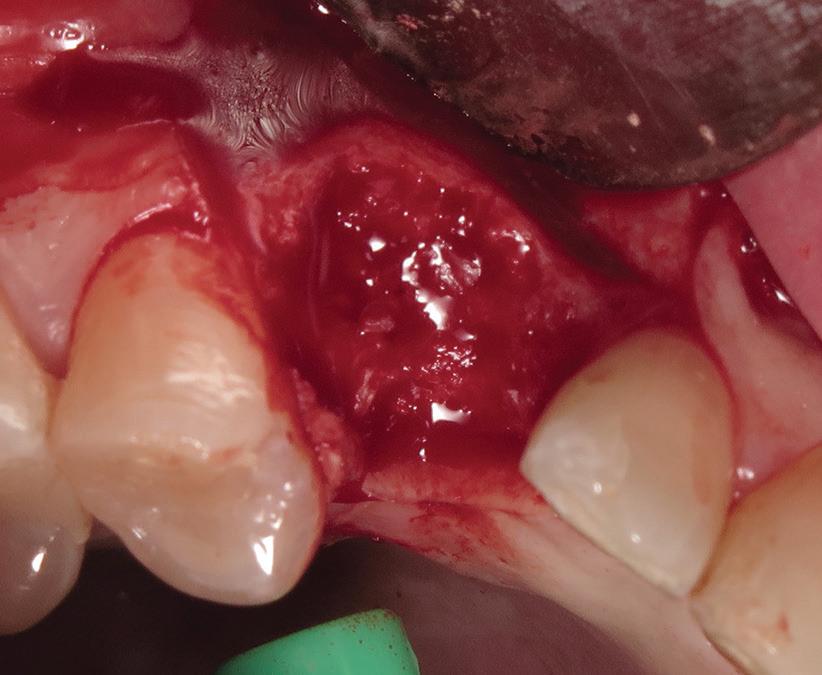

After antiseptic procedures, the surgical site is evaluated. In Fig 4, the site shows good hard and soft tissue volume consistent with that seen in the preoperative planning scans.

Fig 5. The reflected flap reveals bleeding vital bone and maintenance of ridge width.

Fig 4. The fully healed site is ready for implant placement.